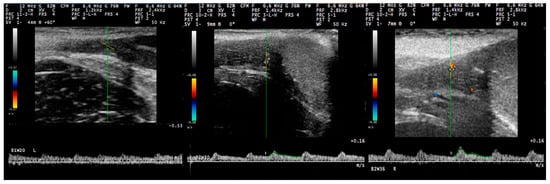

3.2. B-Mode Examination

3.3. Pulsed-Wave Doppler

4.2. Differences in the Findings between the Regions of the Testis